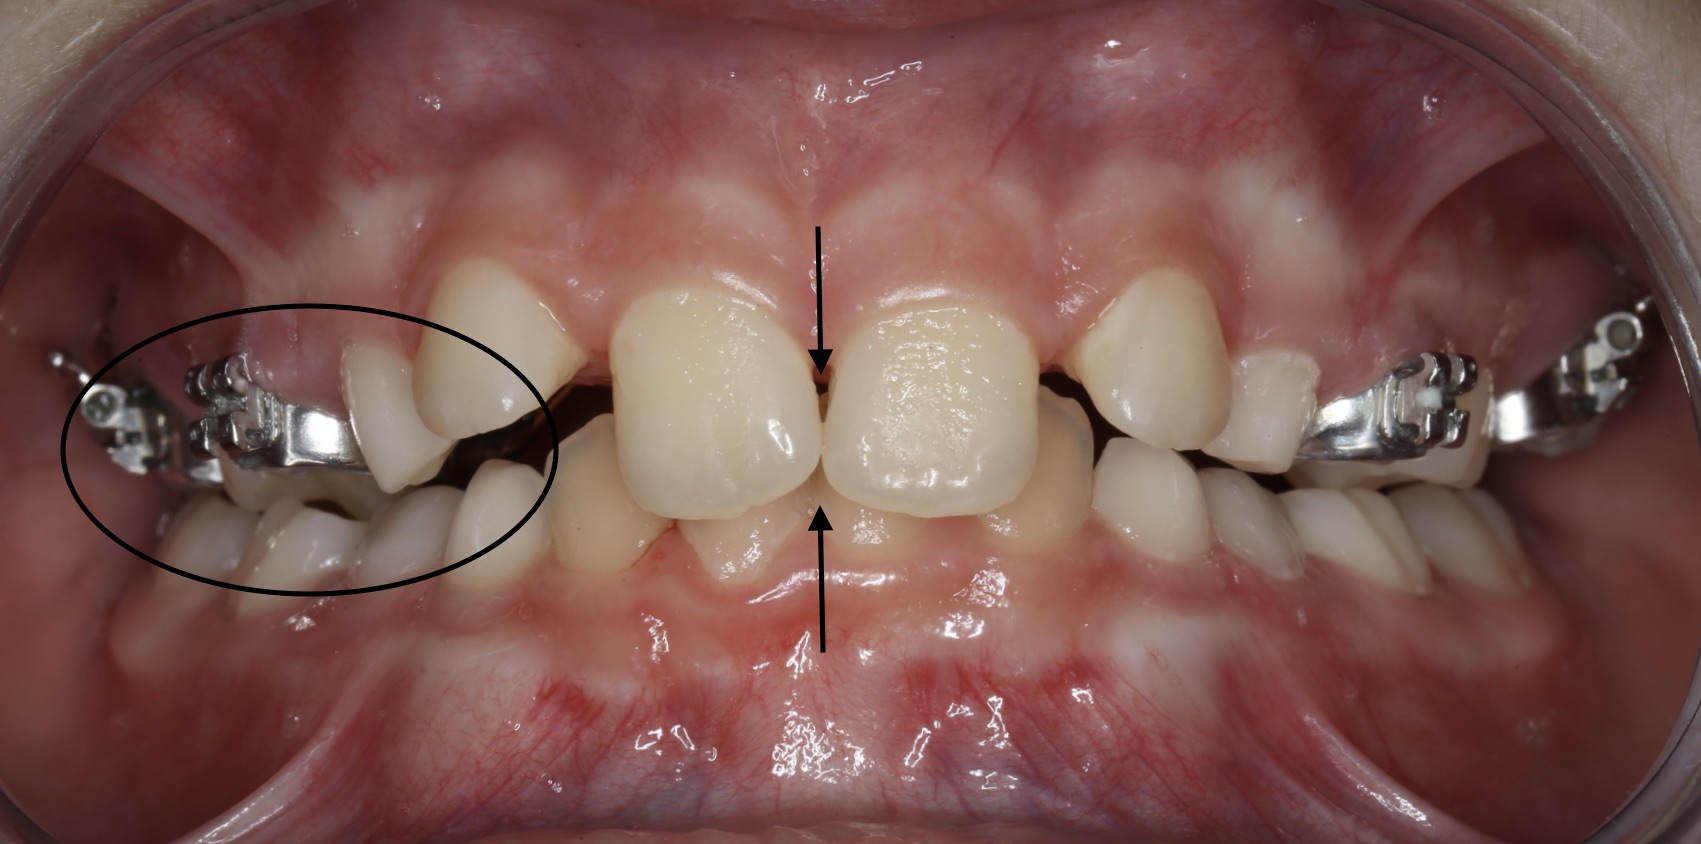

Hier laten wij een voorbeeld zien. Meisje van 10 jaar met een smalle bovenkaak. Hierdoor past de onderkaak er niet goed tussen en bijt ze aan de rechterkant (voor de kijkers links) in een kruisbeet.

De middens van boven- en ondertandboog zijn niet gelijk, omdat ze naar rechts in kruisbeet dichtbijt nu de onderkaak niet recht in de bovenkaak past.